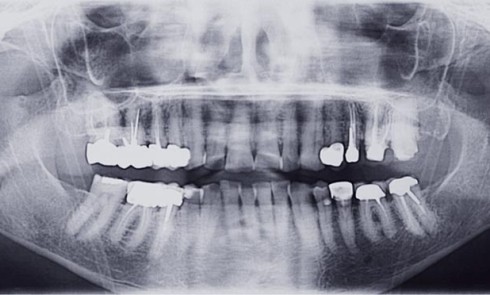

Article réservé à nos abonnés Dossier Orthodontie prothèse

Au cours des trente dernières années, les avancées dans le domaine de la recherche ont permis une meilleure connaissance des...

Article réservé à nos abonnés La demande orthodontique du patient adulte

L’une des clés de la prise en charge des adultes est « le motif de consultation ». Il existe dans...